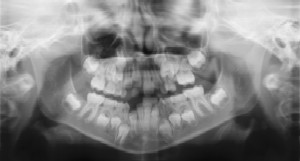

Dental x-rays are an essential part of the diagnostic process. They aid in detecting cavities and pathologies that are not always clinically detectable. They also aid in monitoring the growth and development of the permanent teeth and for orthodontic reasons. Diagnosing dental infection early may help the treatment appointment to be shorter and easier on the patient, resulting in a less traumatic experience. Of course as a pediatric dental practice we are careful not to overexpose children to radiation. Today’s equipment, including digital and high speed films, result in less radiation and make dental radiographs negligible as compared to detecting dental disease earlier. The risk of getting cavities is a multifactorial process that is individual to each patient and Dr. Espinosa will determine the patient’s risk at the initial and follow-up appointments. Depending on family history, anatomy, diet, hygiene, and clinical observation, a child’s first dental x-ray typically occurs between the ages of 3-5. The American Academy of Pediatric Dentistry’s guidelines recommend radiographs at 6 month to 2 year intervals thereafter depending if the patient is high or low risk for dental cavities. If you have additional questions or concerns regarding dental radiography, don’t hesitate to ask!